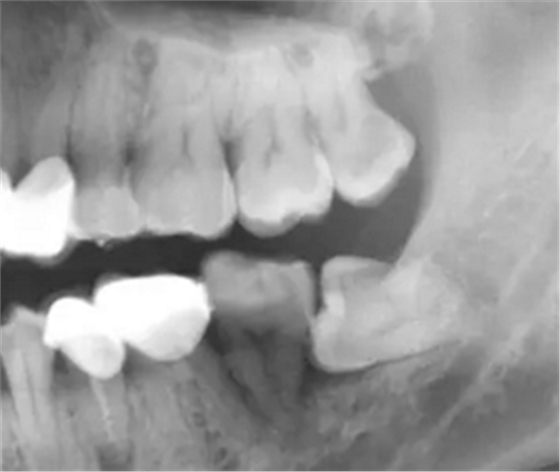

2.牙根折斷。牙根折斷是拔牙術(shù)中常出現(xiàn)的并發(fā)癥,造成牙根折斷的原因很多。如:所拔牙的牙冠破壞廣泛,或有較大充填體,對于一些老年人的牙,死髓牙,根管治療后的牙,牙體組織的脆性大,容易折斷,牙根外形變異,出現(xiàn)彎曲,根端肥大,粗大多根,額外根,根分叉過大等情況,根周骨質(zhì)因各種病理生理因素(慢性根尖炎,老年人等)致密性,造成彈性降低或牙根固連等都容易造成牙根折斷(對于短小的小于5mm的短根,根周無炎癥,取出創(chuàng)傷大者,可不拔除,后期觀察)。

防治:牙拔除術(shù)后應(yīng)仔細(xì)清理牙槽窩,特別是慢性根尖周炎的患牙,根尖炎性病灶不刮治干凈,即可發(fā)生拔牙術(shù)后出血,也可形成慢性炎癥而長期不愈。多根牙拔除時應(yīng)防止殘根遺留。如發(fā)生慢性感染,應(yīng)拍攝X線片,了解牙槽窩內(nèi)病變情況,是否有異物遺留,牙槽窩的愈合情況等,然后在局麻下,重新進(jìn)行牙槽窩的刮治,讓血液充滿后,消毒紗布棉卷壓迫止血,并給予口服抗生素治療。